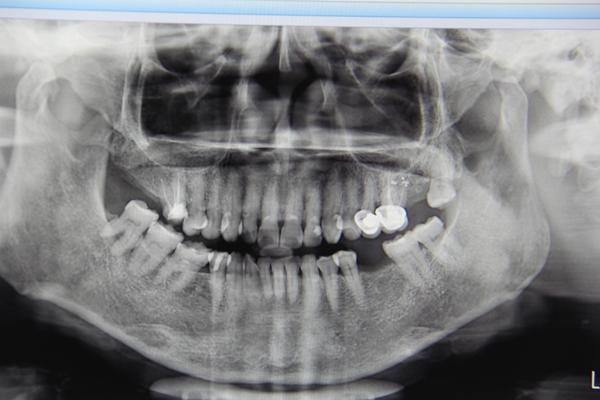

今天参与手术直播的是一位67岁的郑阿姨,手术医生冯医生为郑阿姨种植的是左下第6颗牙齿。在手术开始前,专家对郑阿姨的牙齿情况进行了会诊。

郑阿姨的牙齿拍片情况